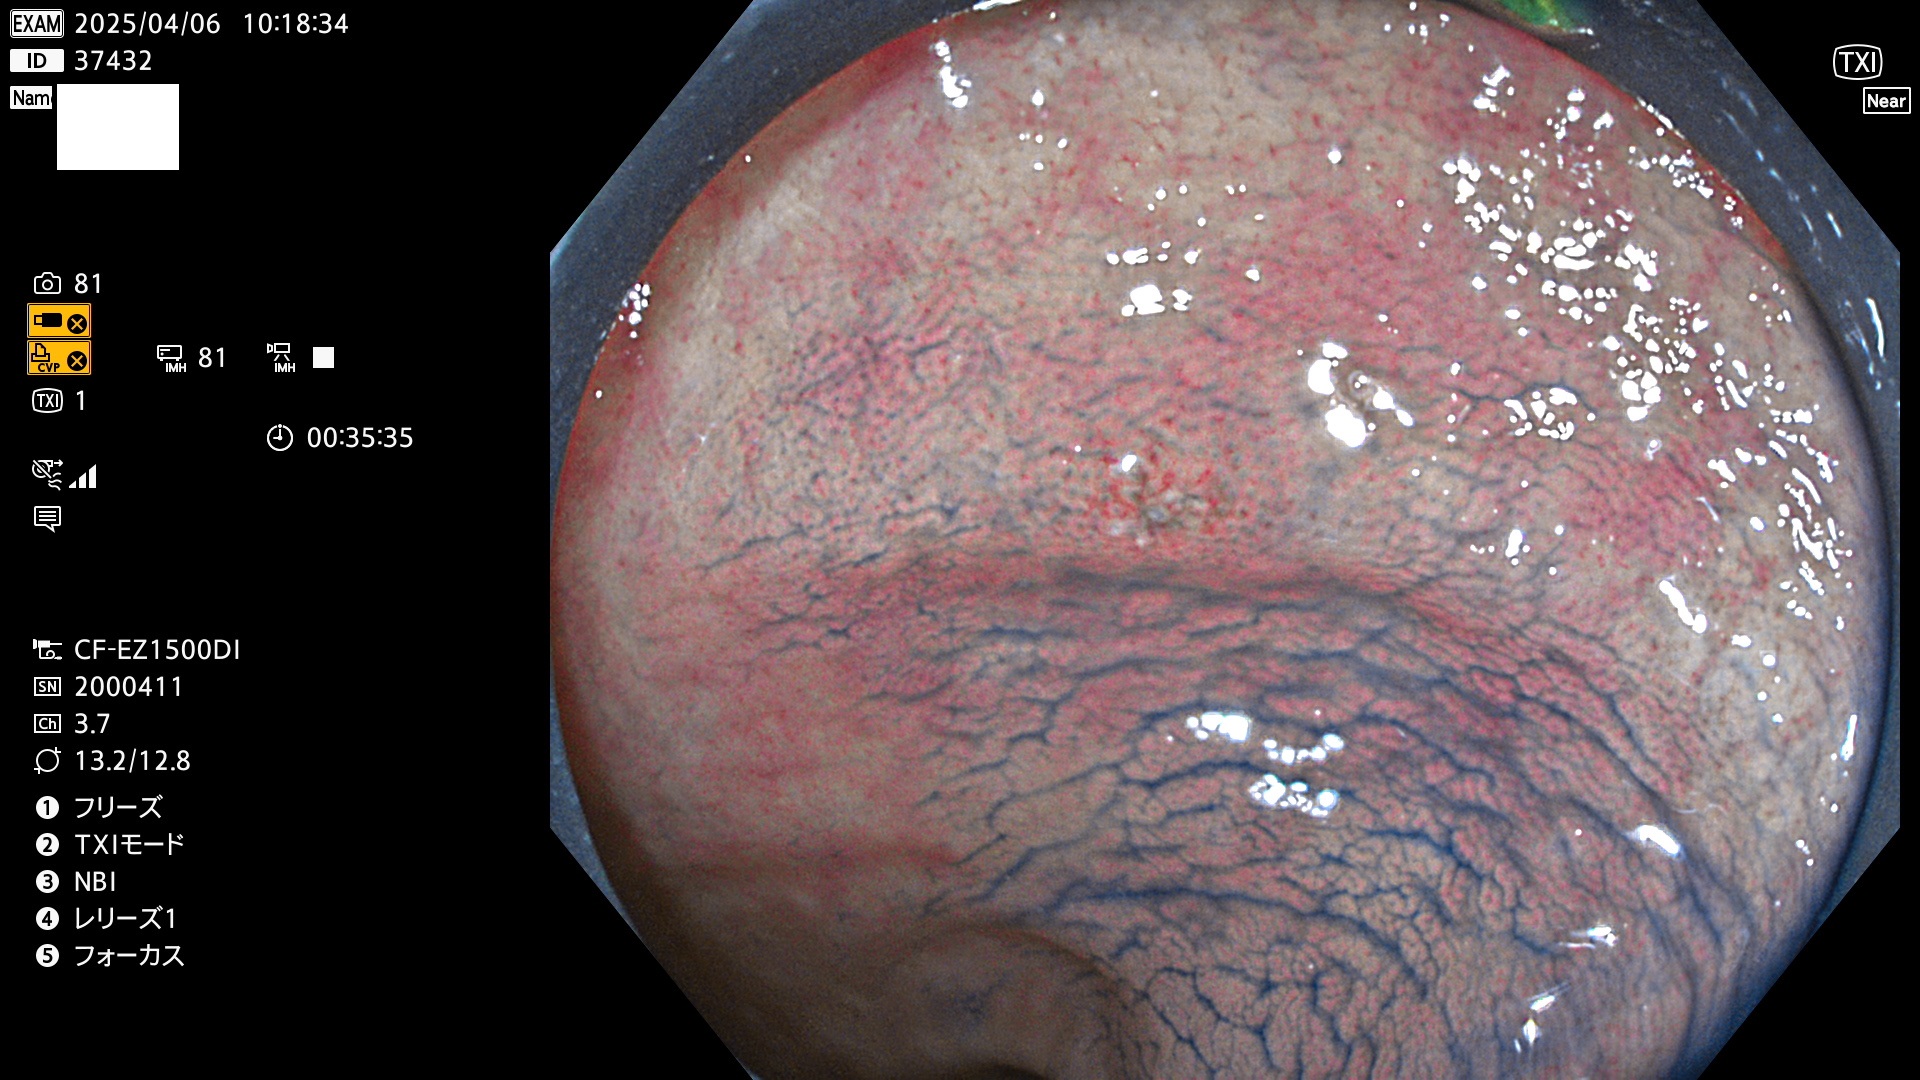

以下は当院で経験した「ビランと鑑別の難しいUc型腺腫」です(全て、病理で腺腫を確認済み)。

このような病変は表面を拡大観察しても診断は不可能であり、現在の内視鏡診断の「限界を超えた病変」と言えます。現実的な対策は「典型的なビランと異なる」と感じたら、「コールド法で積極的に切除する」ことと考えます。もちろん「結局はビランだった(不要な過剰切除だった)」ということもあります。しかしコールド法なら重篤な合併症は稀であり、医師は切除を躊躇すべきではないと考えます。